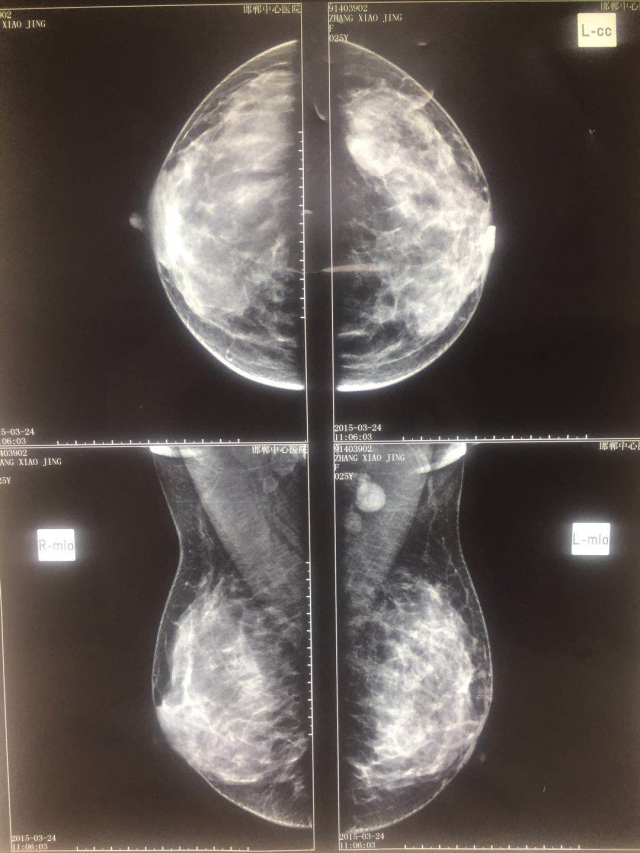

我院乳腺钼靶片:1 两乳多量型腺体型;2 两乳增生症,请结合临床,必要时及时复查;3 左乳外上团片影。考虑占位不除外,请结合临床,建议进一步检查。

2015-03-24